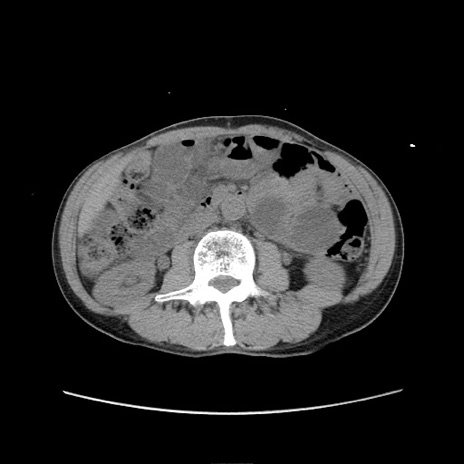

症例11(横断像)

【症例】 60歳代男性

【主訴】 下腹部痛

【現病歴】 本日夜中より下腹部痛の症状認め、受診。

【既往歴】 膀胱癌(膀胱全摘+尿管皮膚瘻術) 、胃癌術後

【身体所見】 BT 35.3℃、PR 58/min、BP 136/98mHg、腹部平坦、軟、腸蠕動音±、ストマ留置あり、左上腹部~正中部に圧痛あり、反跳痛なし。

【データ】WBC 5100、CRP0.01